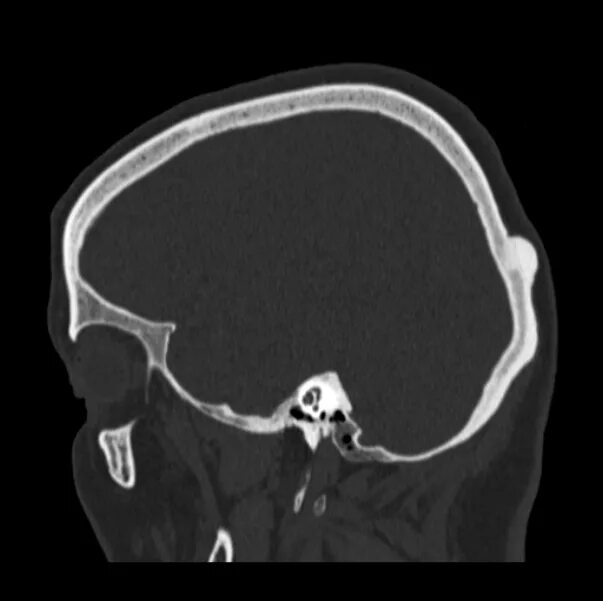

Череп на кт